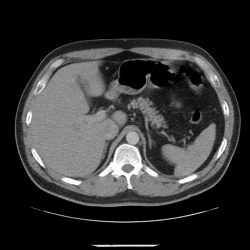

26.05.2014 - 19:31

Женщина 41г. поступила в ХО, жалобы на слабость, сниженный аппетит, боль в правом подреберье. Значительно снижена плотность печени от +10 до -2HU. Стеатогепатоз? Натив